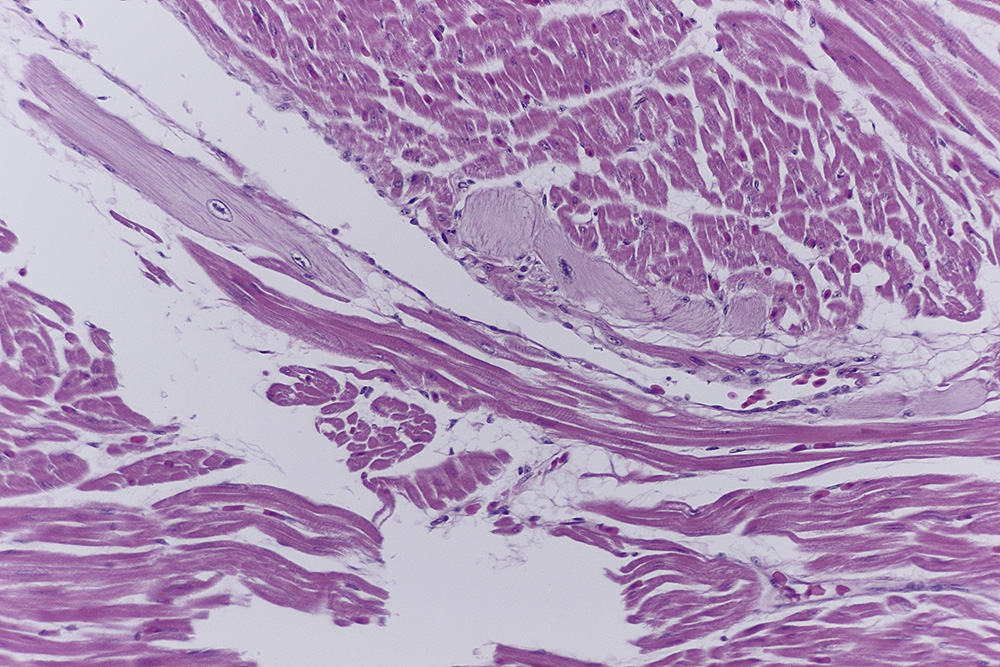

Die Purkinje-Fasern als spezialisierte Herzmuskelzellen, bilden den letzten Teil der

Impulsleitung mit direktem Übergang in die Myocardzellen.

Diese, oft als ,,Möpse" beschriebenen Zellen, liegen im Inneren der Herzkammern

zwischen Endocard und Myocard in einer Schicht aus lockerem Bindegewebe zusammen

kleinen Blutgefäßen und nicht myelinisierten Nerven.

Abb.2: Purkinjefasern 1, Endocard 2

Abb.3